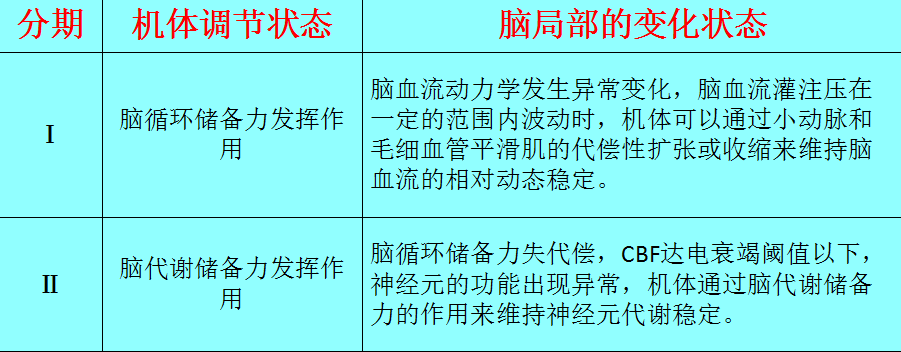

表1 脑局部缺血的病理生理变化

表2 脑梗死前期脑局部缺血影像分期